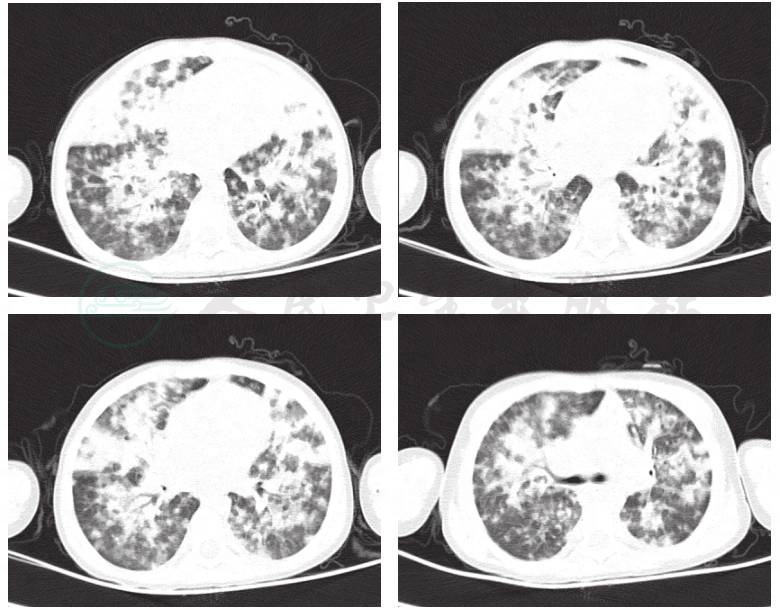

入院后,患儿根据发热伴有咳嗽,考虑存在肺部感染,因病原尚不明确,经验性给予患儿头孢甲肟联合红霉素抗感染治疗。并予患儿卧床休息、低流量吸氧、止咳化痰药物等对症支持治疗。予患儿床旁监护观察生命体征变化,并根据病情分析完善相关检查。根据化验结果回报:血常规:白细胞9.0×109/L,血红蛋白105g/L,血小板59×109/L;C反应蛋白18.50mg/L;降钙素原0.394ng/ml;提示细菌感染依据不足。根据病原学化验回报:EB病毒EA-IgG抗体阳性,EB病毒VCA-IgG抗体阳性,而其他病原检测,如肺炎支原体抗体、肺炎衣原体抗体、巨细胞病毒抗体、单纯疱疹病毒抗体、病毒抗体八项及G试验,均为阴性;考虑患儿除EB病毒感染外无其他常见致病菌感染征象;予患儿加用静滴更昔洛韦抗病毒。化验回报结核斑点试验阴性,请胸科医生会诊,暂不考虑现正结核感染。此外,患儿总蛋白49.9g/L,白蛋白21.3g/L,予阿拓莫兰保肝及白蛋白支持治疗;肌酸激酶1267U/L,肌酸激酶MB同工酶79U/L,予磷酸肌酸钠营养心肌。此外,根据淋巴细胞亚群回报:CD4+T淋巴细胞计数<32个/μl,下降极为明显,提示患儿免疫功能异常;且患儿具有较特征性的影像改变(图1);立即予患儿完善HIV初筛试验。

图1 入院后肺CT结果

诊断依据:①患儿咳嗽、发热及呼吸困难的症状;②肺部闻及水泡音;③CD4+T淋巴细胞计数<32个/μl,HIV-1型抗体阳性,且具有较特征性的影像改变。确诊依靠病原学检查,如痰液或肺泡灌洗液等发现肺孢子菌的包囊或滋养体。患儿病情危重,暂不能耐受以上检查;待患儿病情稳定后完善以上检查进一步明确诊断。

艾滋病并发卡氏肺囊虫肺炎的病理为:患者体内弥漫性、嗜酸性的浆液渗出体外并且伴随有泡沫状的改变,之后,与患者病灶间(间质增厚)进行融合,从而使得其有机化、纤维化,从而在CT影像中呈现双肺网状影、双肺弥漫毛玻璃影。艾滋病并发卡氏肺囊虫肺炎的诊断标准:CD4+T淋巴细胞计数<200个/μl;起病隐匿或亚急性,干咳、气短和活动后加重,可有发热、发绀,严重者发生呼吸窘迫;肺部阳性体征少,或可闻及少量散在干、湿啰音,体征与疾病症状的严重往往不呈正比;胸部X线或CT检查可见双肺从肺门开始的网格状结节样浸润,有时呈毛玻璃阴影;血气分析示低氧血症,严重病例动脉血氧分压明显降低,常在60mmHg以下;乳酸脱氢酶常升高;确诊依靠病原学检查如痰液或肺泡灌洗液等发现肺孢子菌的包囊或滋养体。

卡氏肺囊虫肺炎X线表现:早期X线表现为无明显异常或仅表现为肺纹理增粗、肺透亮度下降,有部分患者早期胸部X线片显示正常;随着病情进展,X线表现主要为双肺对称或不对称磨玻璃状阴影或实变影,以肺门区、中下肺野为明显,可伴有支气管充气征,病理基础为肺泡渗出性炎症;至晚期病灶累及肺间质,发展为肺门周围和/或基底段网状或网状结节浸润病变,或伴整个肺部弥漫性均匀性实变,其病理基础为渗出性肺泡炎合并肺泡壁及小叶间隔增厚,并有炎症细胞浸润。由于X线片重叠多,分辨率有限,一些细微间质结构观察并不清晰,因此螺旋CT特别是高分辨率CT的应用,能提供更多有价值诊断信息。高分辨率CT对病灶特征显示尤佳,具有较特征性的影像改变:①肺内毛玻璃样是其特征性表现,病变以肺门为中心分布,呈斑片状或地图状分布,伴有网状影,病变区与正常肺野交错存在,有融合倾向,其间可见支气管血管束。②斑片实变型:较常见,多在肺段或亚段发生,常表现为双侧不均匀斑片状模糊阴影。③间质型:显示双侧间质纹理增多,最初为线状或网状的二级小叶间隔增厚,可均匀,也可不均匀。④显示肺气囊的分布及其融合趋势。气胸的发生率增加可能与囊腔的出现和融合密切有关。⑤尚可有非典型表现为网格状阴影、粟粒阴影、多发小结节、胸内淋巴结肿大、气胸、肺内空洞和少量胸腔积液。如未经适当治疗发展为急性呼吸窘迫综合征。